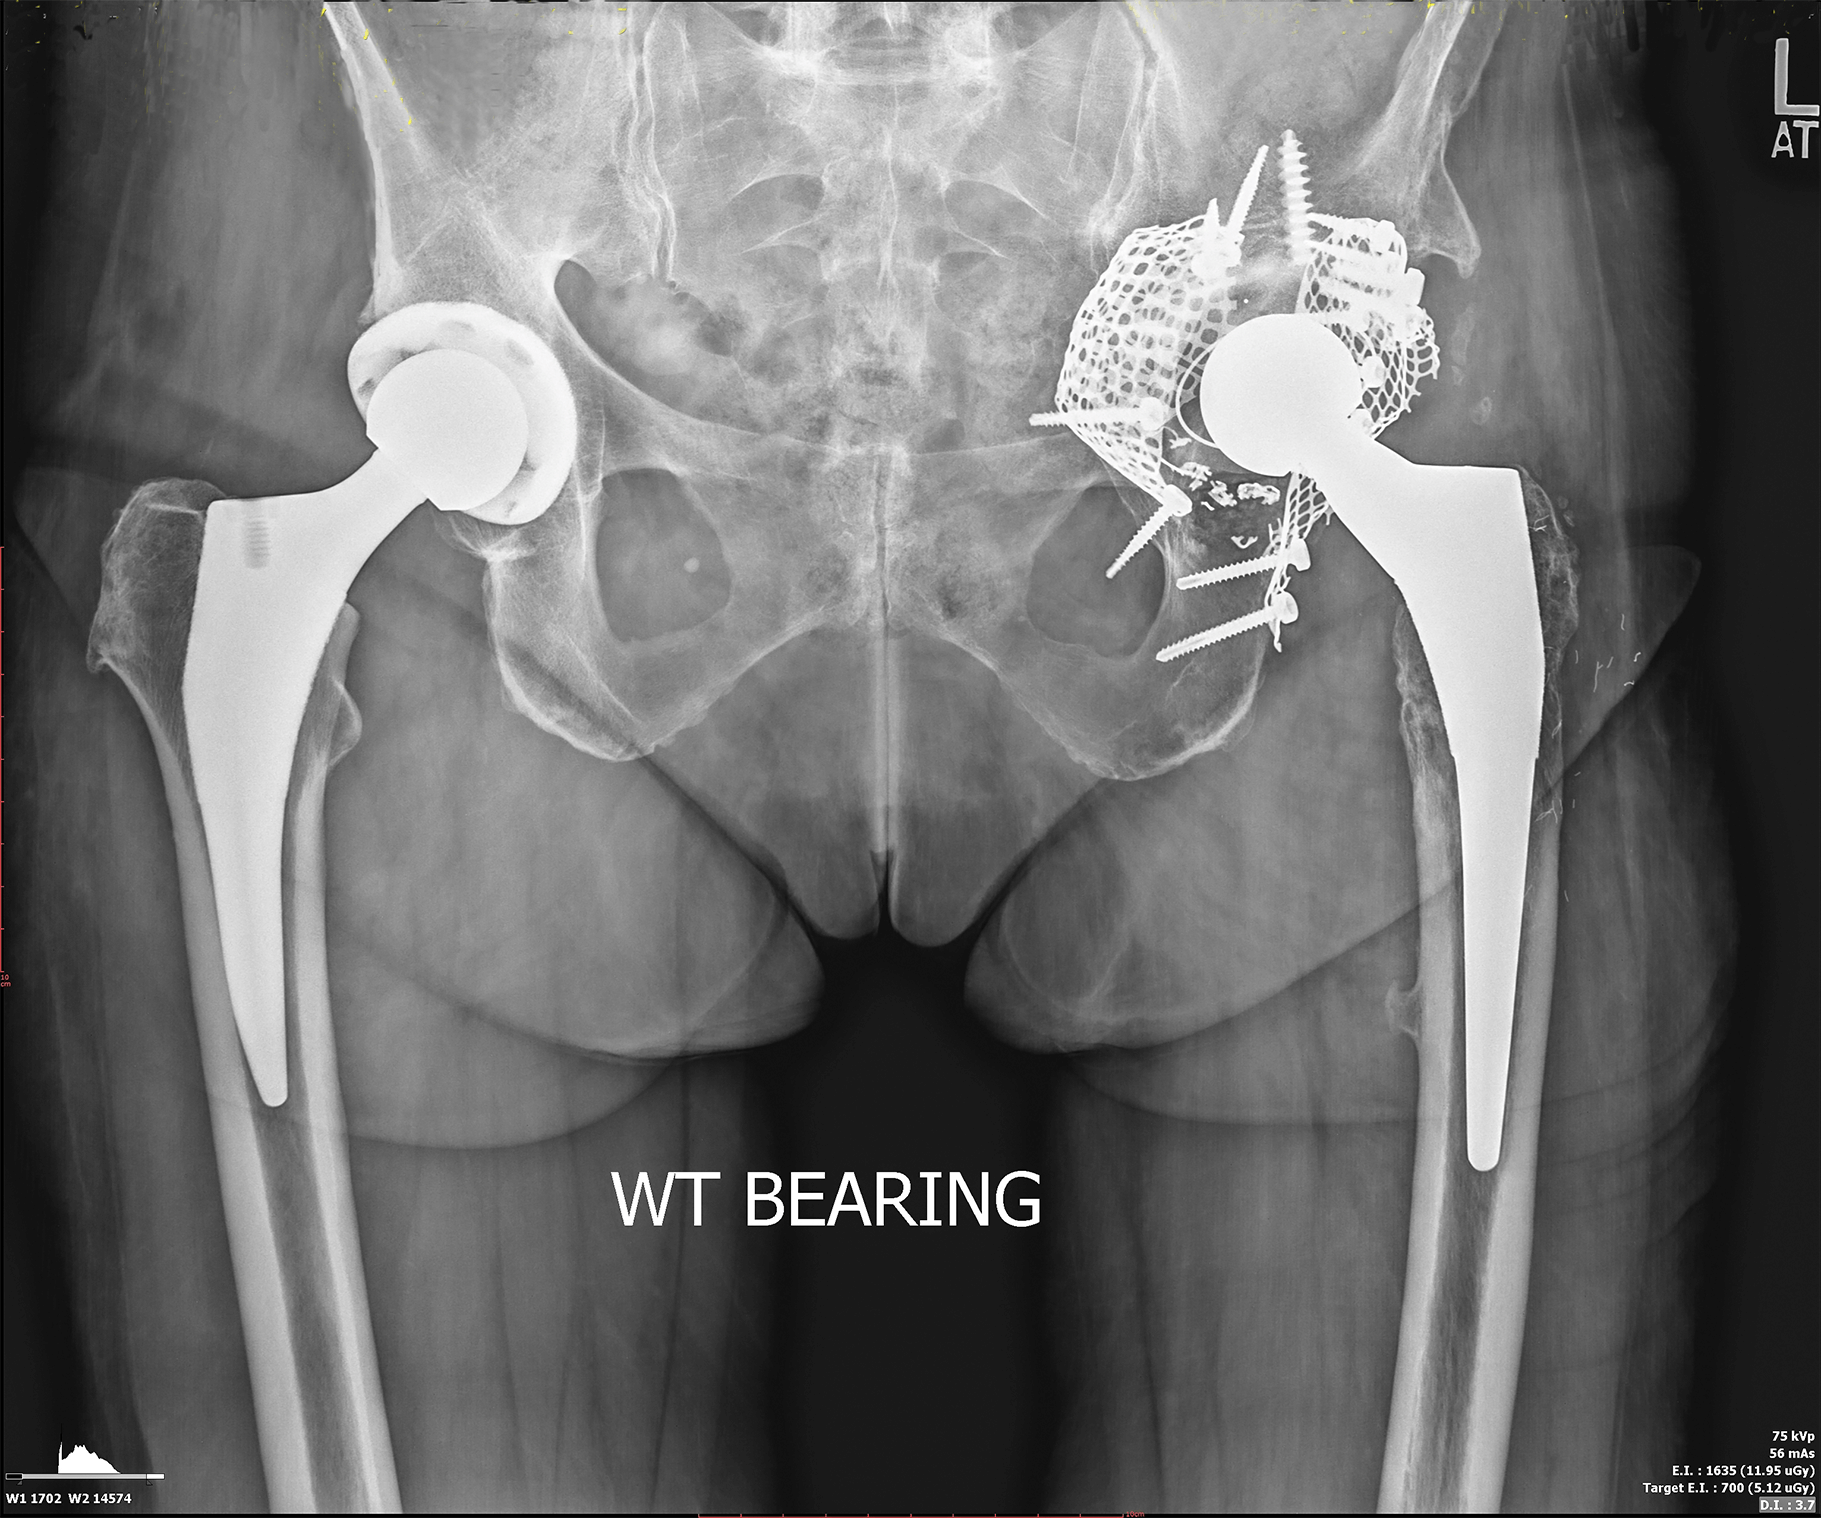

Bethany 73 years, had received a total hip replacement on both sides.

On the left side she needed several revisions and suffered from various dislocations. Now, she shows up with a pelvic fracture and loosening of the left acetabular cup.

customLINK used the CT data of the defect situation within Bethany‘s pelvis to create a 3D model of the anatomy. Based on this, an acetabular replacement was designed that uniquely fits into the defect and restores the hip joint.

Anchorage of the implant was provided by three flanges that are fixed with numerous cortical screws, as well as a strong cranial cancellous screw within the ilium.

A cemented acetabular polyethylene inlay was planned to articulate with the hip head.

The post-operative X-ray image shows the fit of the implant within the defect, the anchorage with one strong, cranial cancellous screw ("home run screw") and the attachment of the flanges. To keep the tissue damage minimal, the acetabular net and some screws were left in situ. The hip stem was additionally stabilized with cerclage wires.